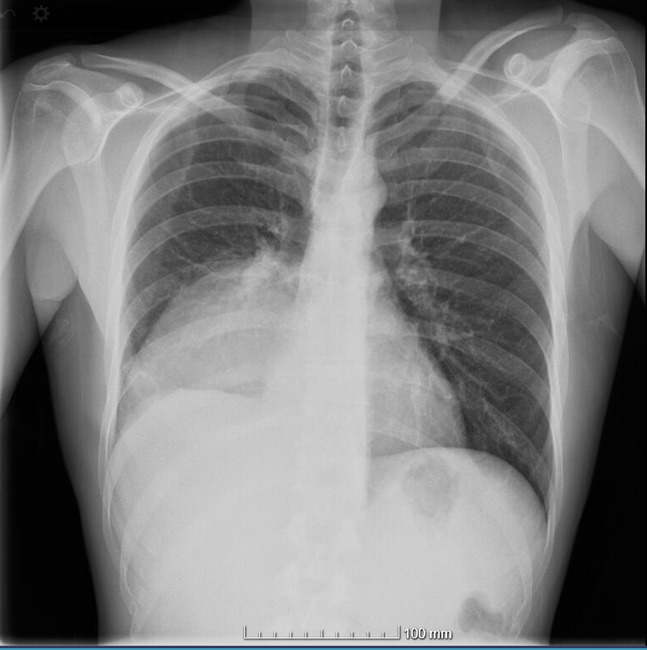

Se realiza una radiografía de tórax informada como atelectasia basal derecha. El paciente es ingresado en planta de Neumología. Realizan un TAC de tórax con contraste, que confirma un derrame pleural compatible con empiema como primera posibilidad. El paciente evolucionó favorablemente tras antibioterapia y drenaje de 750 cc de material purulento, con mejoría clínica y radiológica. Fue dado de alta a domicilio con el diagnóstico de empiema pleural derecho, probablemente secundario a diseminación hematógena por boca séptica.

La ecografía supone un complemento a la exploración física que puede ayudar de manera decisiva en la toma de decisiones, diagnóstico y seguimiento evolutivo; a veces con mayor rentabilidad que la radiografía, como es nuestro caso.